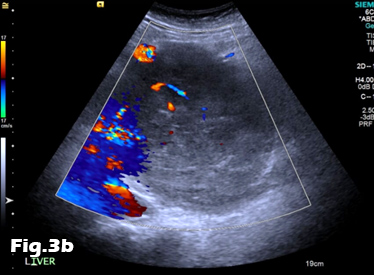

We present the case of a 59-year-old male, previously fit and well who presented to the General Practitioner with a 3 week history of epigastric pain, shortness of breath and unintentional weight loss. On examination, there was evidence of abdominal distension and palpable swelling of left testes. Initial investigation with US of the scrotum revealed dilated (maximally 5.3mm) left pampiniform plexus with retrograde flow on Doppler ultrasound and Valsalva manoeuvre, consistent with an extensive unilateral varicocele (Fig. 1 and 2). Subsequent abdominal ultrasound demonstrated moderate ascites, dilated common bile duct, large right sided pleural effusion and a large 14x14cm solid, vascular epigastric mass. This prompted urgent surgical referral and further cross-sectional imaging (Fig. 3). CT abdomen showed a large soft tissue density retro-peritoneal mass obliterating the portal mesenteric vein circulation and causing the left varicosity (Fig. 4). Ultrasound guided biopsy of the central abdominal mass confirmed a Stage IV Mantle cell Lymphoma.

Figure 3:A, B: Abdominal ultrasound images revealing the presence of a heterogeneous epigastric mass demonstrating internal vascularity on Colour Doppler imaging.